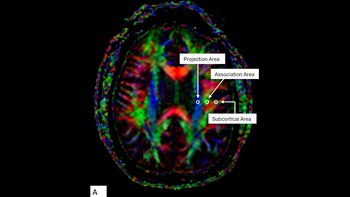

Se utilizó una resonancia magnética especial llamada DTI-ALPS, capaz de mostrar cómo funciona el sistema glinfático.

Este análisis permitió a los investigadores relacionar el funcionamiento glinfático con el historial de golpes y nocauts de cada participante. Así, se pudo observar qué pasa en el cerebro después de muchas peleas.